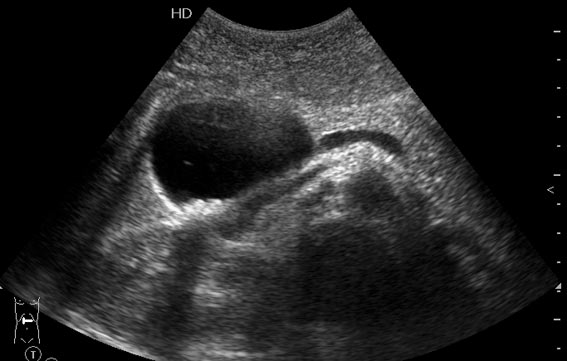

УЗИ, дивертикул холедоха

Молодая девушка, периодически бывают приступообразные боли в животе, преходящая желтуха.

По локализации-киста головки панкреас.Несколько расширен Вирсунг проток(частичный блок).Наличие камней в кисте сначало склоняло к ж.пузырю,но нет ни цистикус,ни Порт.вена,зато как-то "срезана" гловка панкреас этой кистой. Могут быть камни и в старой кисте панкреас.Периодическая желтушность заставляет посмотреть дуоденоскопически что делаеться со сф.Одди и папила Фаттер

Мне кажется, что это все-таки желчный пузырь, а не киста, хотя по одному снимку трудно определить. Вирсунгов проток я не вижу (подозреваю, что то, что besliu приняла за проток - воротная вена). Камеи в пузыре небольшие, поэтому они могут попадать в холедох и вызывать желтуху и приступы боли.

Действительно, дивертикул холедоха, холедохолитиаз.